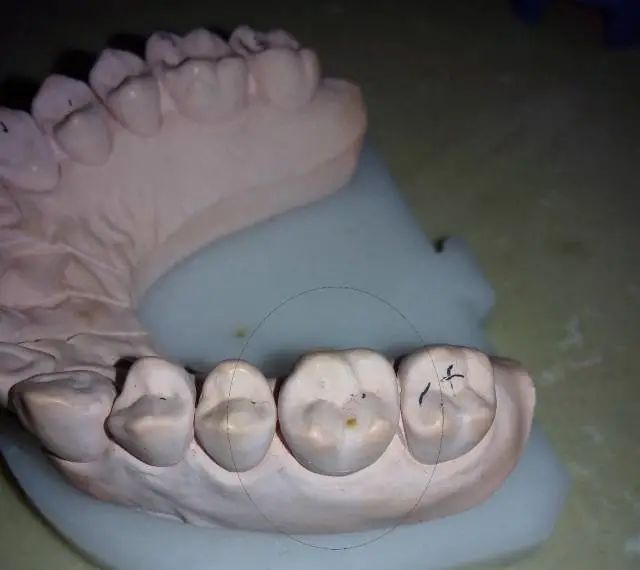

右上第一磨牙 石膏模型

离体牙预备效果